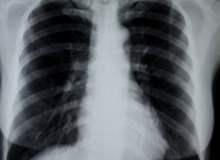

Guatr

Guatrlar boğazın ön tarafında, adem elmasının hemen altında yer alan tiroit bezlerinde oluşan çeşitli tiplerdeki büyümedir. Hipertiroid örneğinde bütün tiroit bezi büyür. Başka bir tipi toksik nodüler guatrdır ve tiroit bezinde bir veya daha fazla no